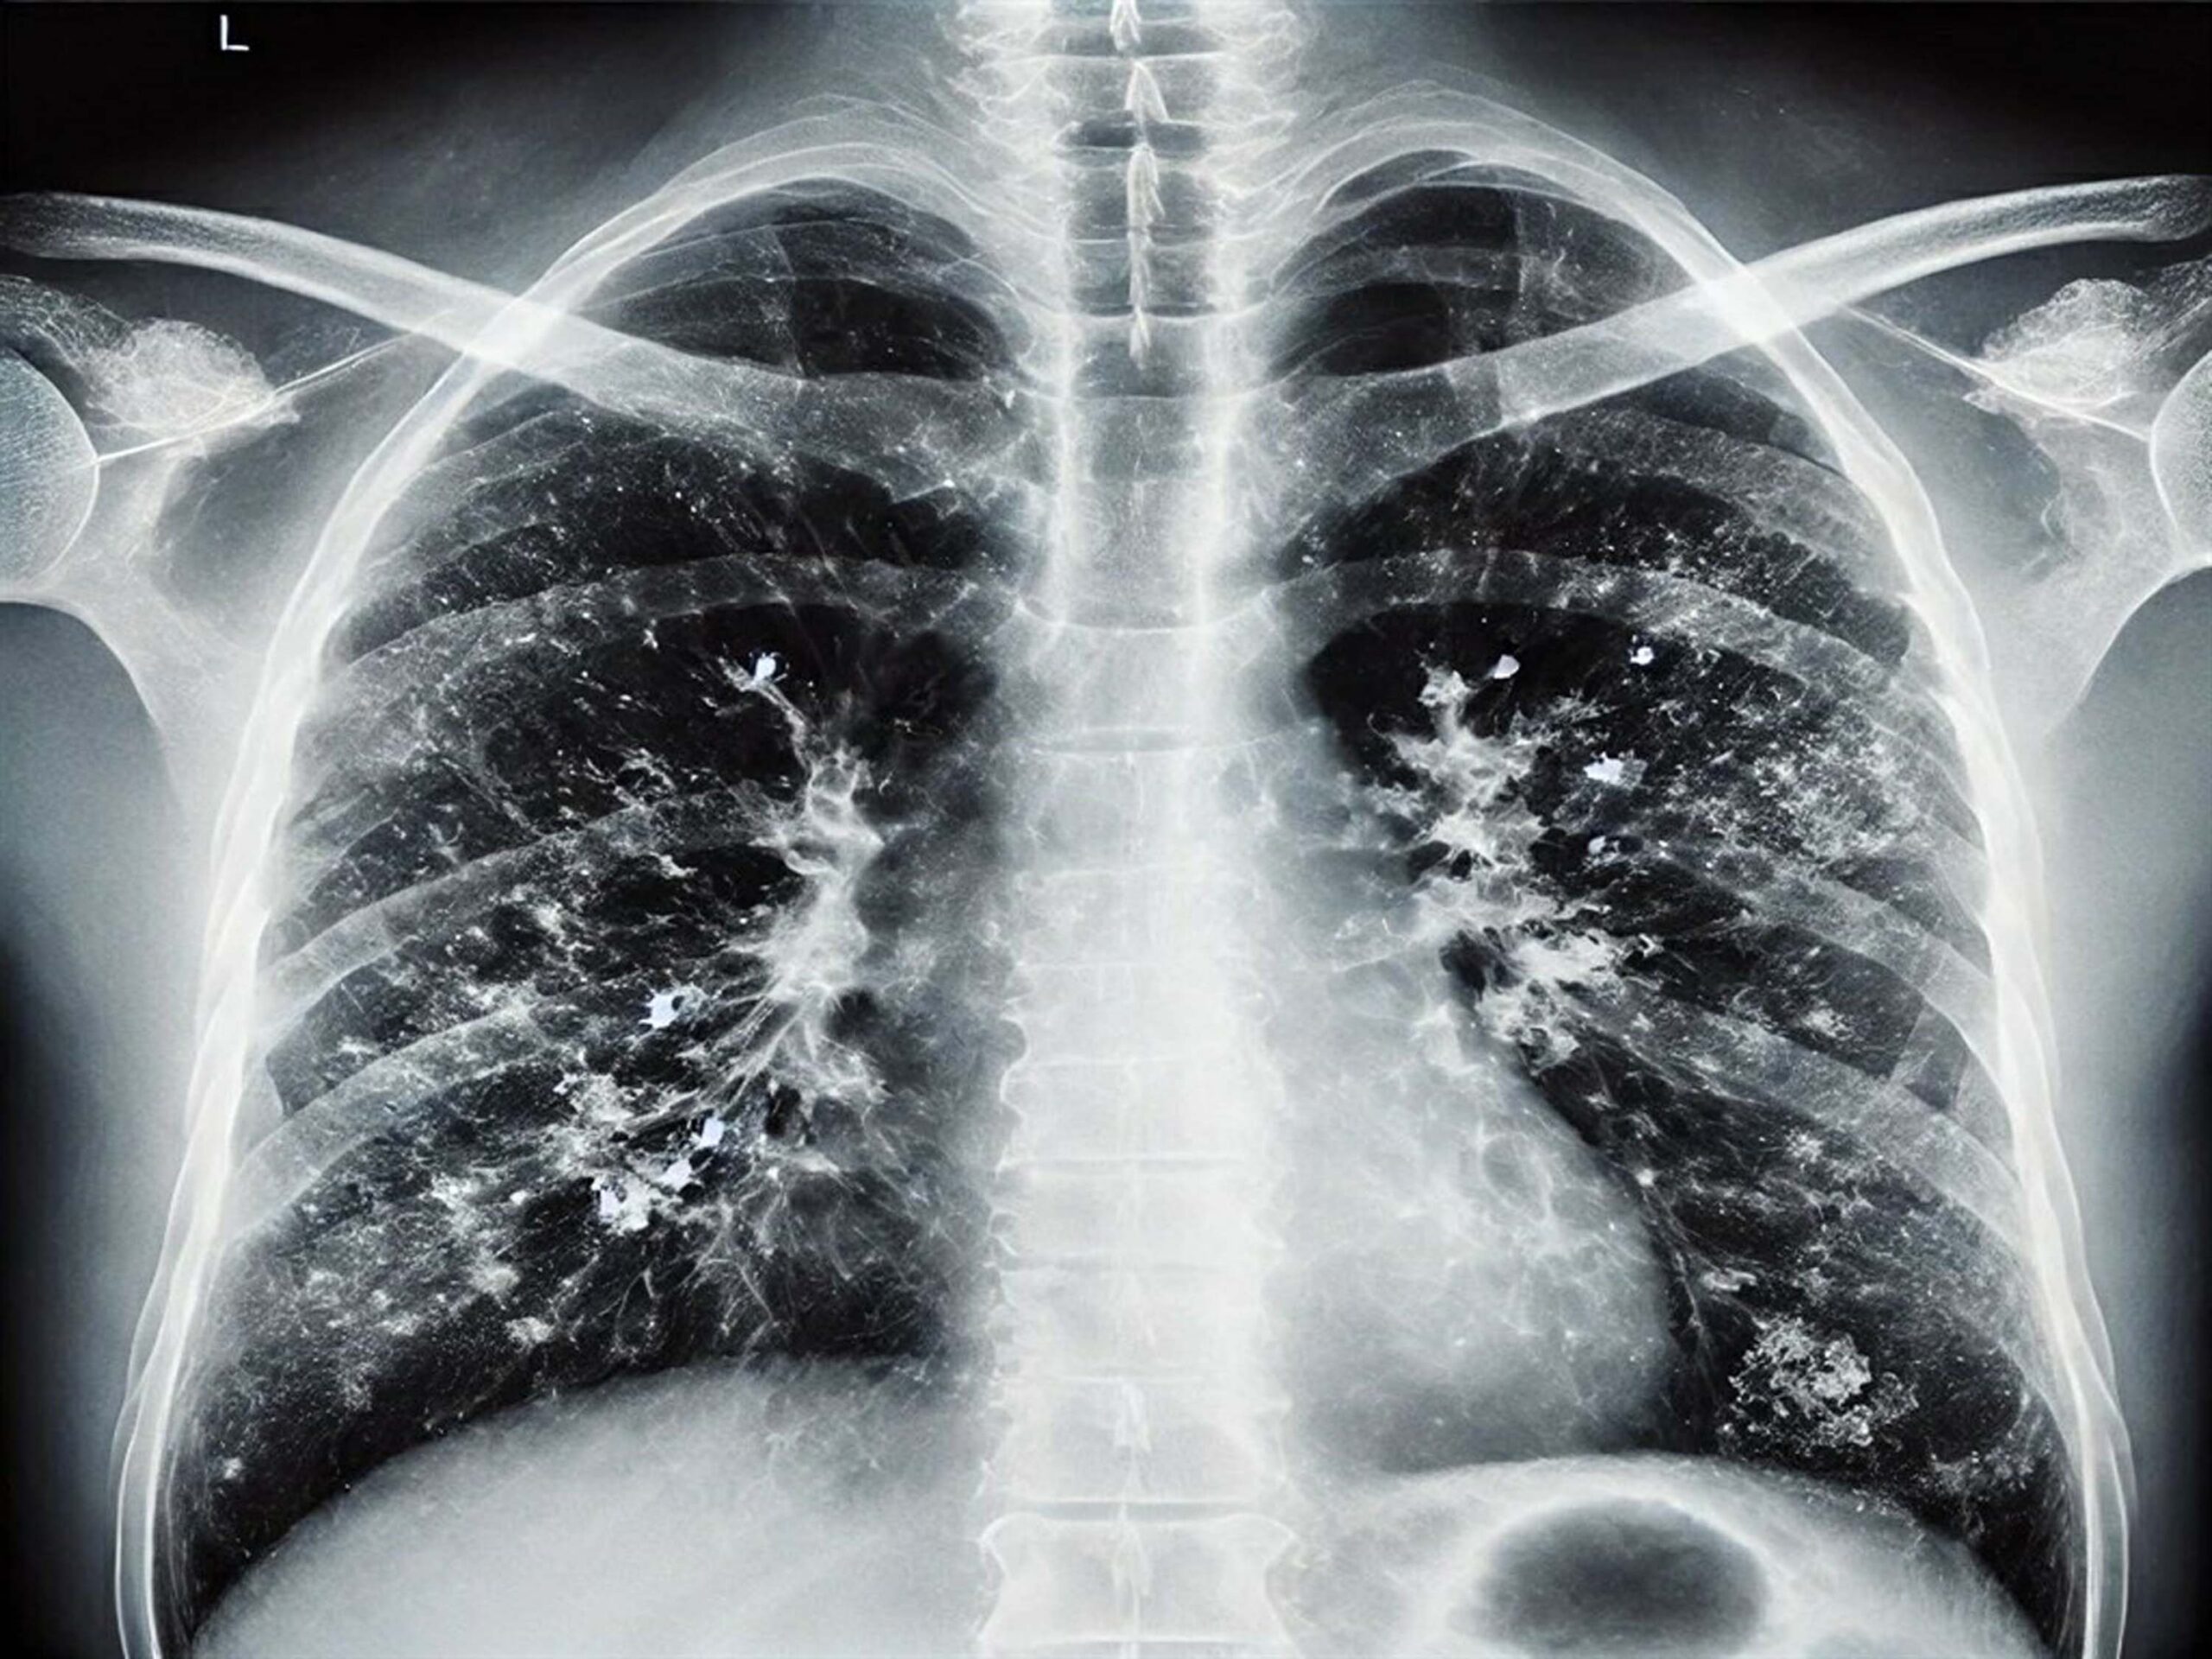

• Doktor Metin Kızılelma, kış aylarında solunum yolu enfeksiyonlarında artışın doğal ve bu enfeksiyonlardan korunmanın en önemli etkenin 'hijyen' olduğunu söyledi. Fotoğraf:Arşiv/İzmir,(DHA)